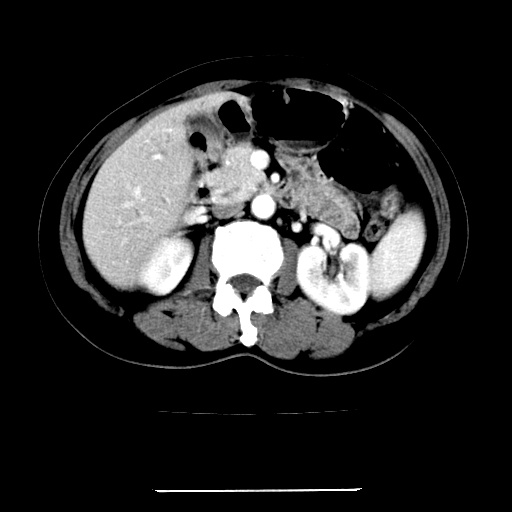

标题: CT22301:女,67岁,上腹部疼痛一周伴皮肤黄染,无发热。 [打印本页]

女,67岁,上腹部疼痛一周伴皮肤黄染,无发热。

左叶肝内胆管结石,并远端肝内胆管扩张。

考虑:肝内胆管结石继发肝内胆管扩张,右肾旋转不良。

肝内外胆管结石并肝内胆管扩张。

建议薄层观察,除外肝门部胆管细胞癌

考虑肝胆管癌;胰头占位?【形态失常,体积增大】

1、肝门高密度影下层面和胰头层面可见轻度胆管扩张,而静脉和延迟期均未见扫描完胰头,不能完全排除胰头占位。2、肝门部高密度影,考虑钙化或结石。

考虑肝门胆管癌伴门脉左支受侵包埋,建议mrcp进一步检查。